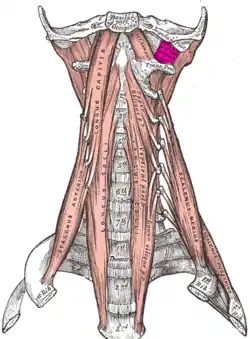

The anterior vertebral muscles. | |

The rectus capitis lateralis, a short, flat muscle, arises from the upper surface of the transverse process of the atlas, and is inserted into the under surface of the jugular process of the occipital bone.